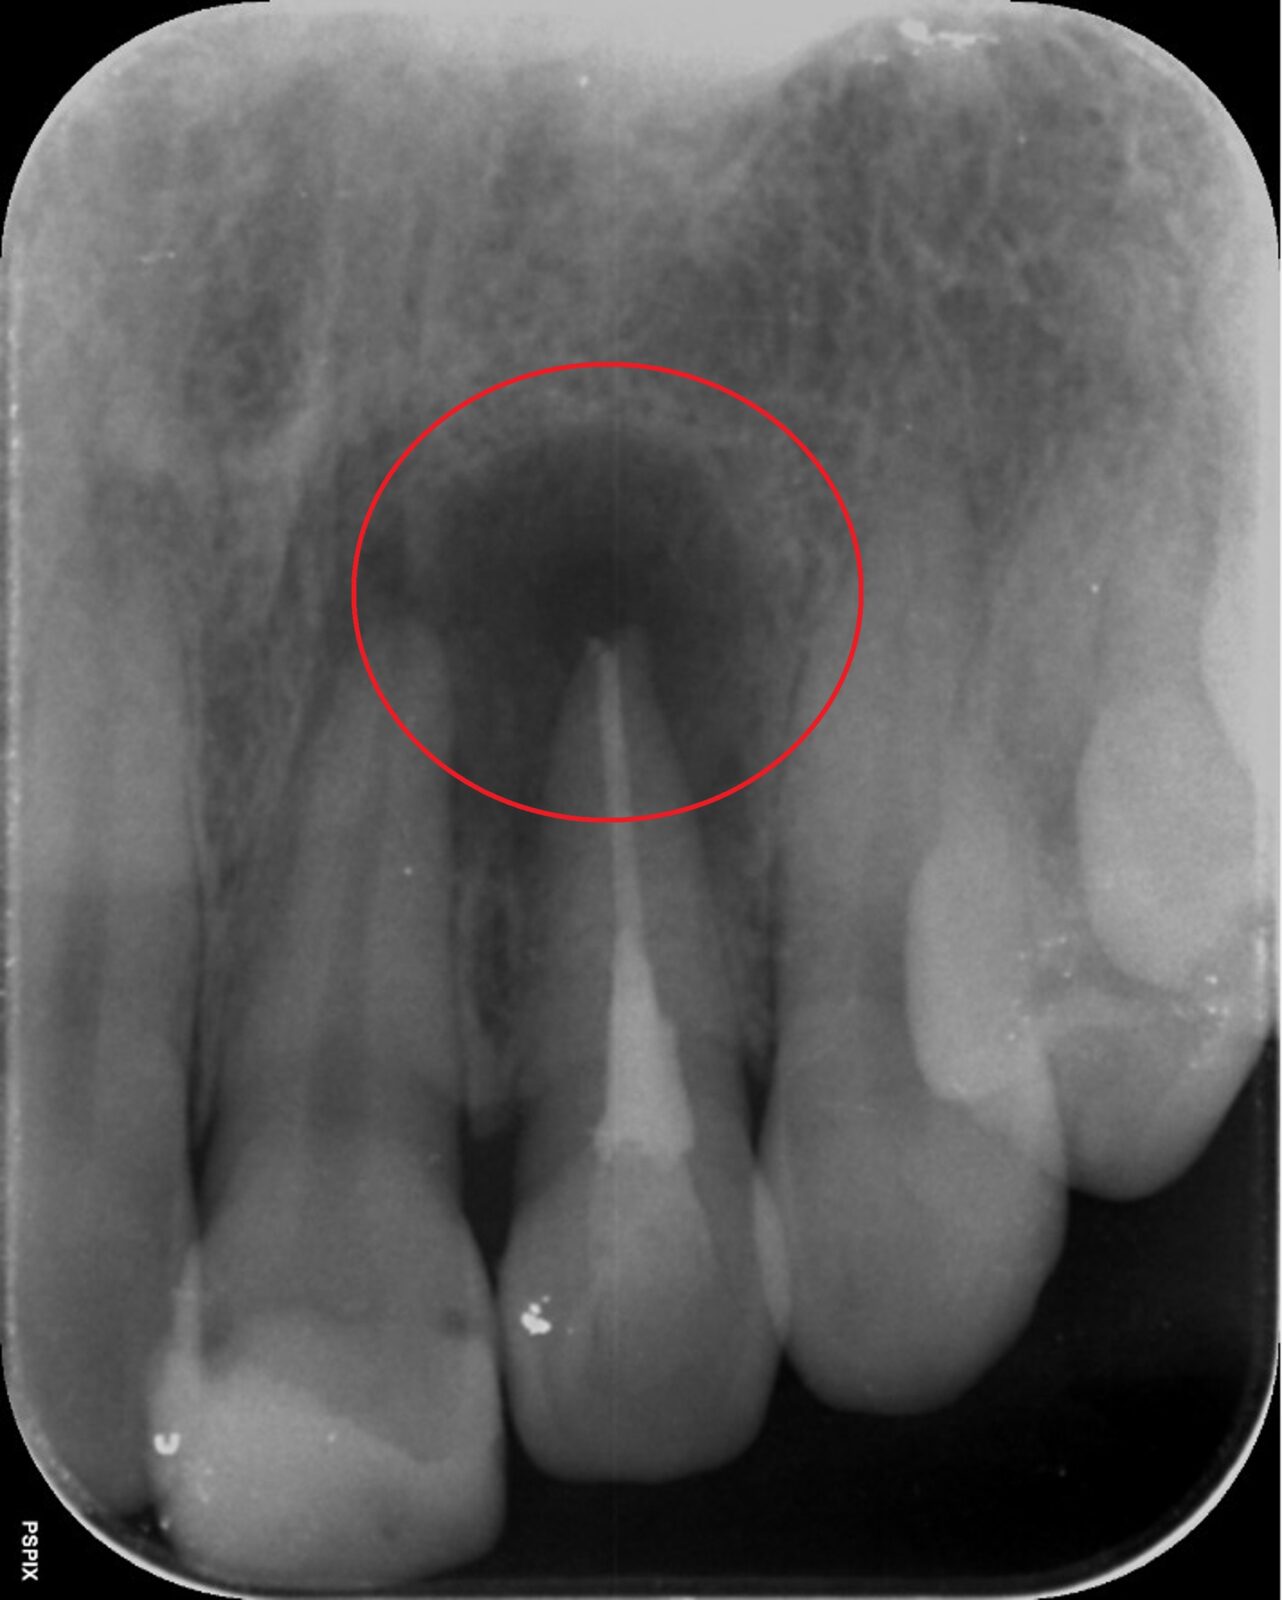

• 治療前

• 治療後

根の先端の炎症を治療する「歯根端切除術」

根の先端に膿が溜まる状況を「根尖病巣」と言います。この状態になると多くが「抜歯宣告」されます。しかし「歯根端切除術」という術式で、抜歯をせずに治療できる場合があります。

歯根端切除術では、歯茎の外側を外科的に切り開き、歯の根の先端ごと膿の袋を取り除きます。取り除いた後の空洞は血液で満たされ、時間の経過と共に再生した骨で埋められます。